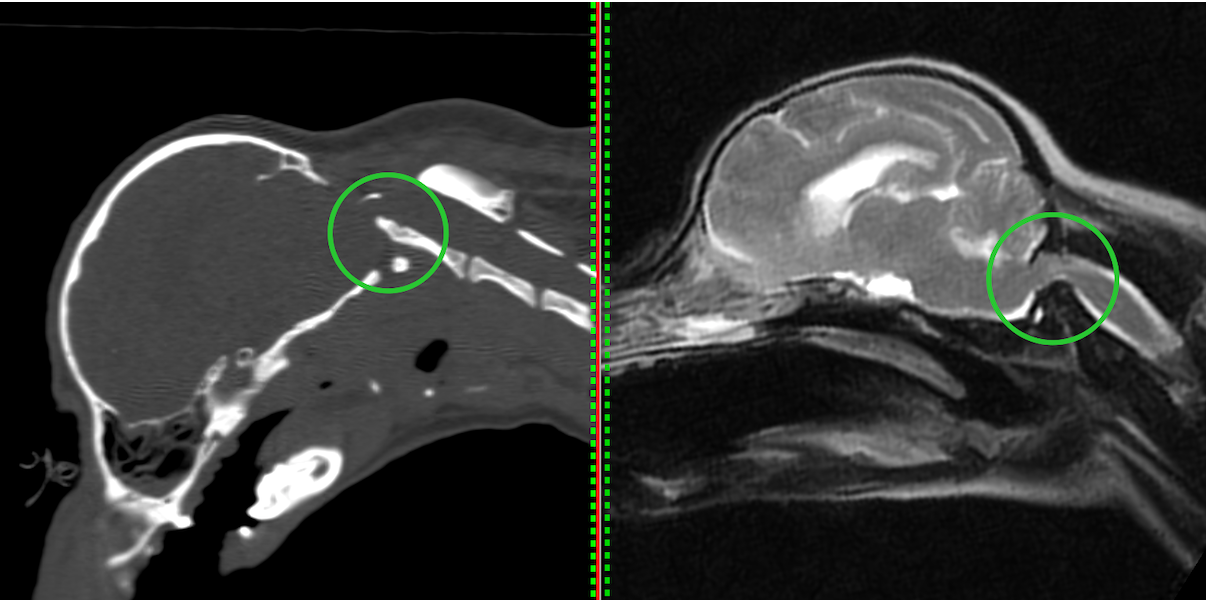

左がCT画像、右がMR画像です。2番めの頚椎である軸椎の歯突起が神経を圧迫してしまっているのがわかります。

CTを3Dにしたものです。立体的に骨の形状(歯突起が不安定になっている)がわかります。また、後頭骨の一部が欠損しています。

MRIでは重度に脊髄が圧迫されており、環軸椎の部分で脊髄が重度に狭窄しているのが分かります。